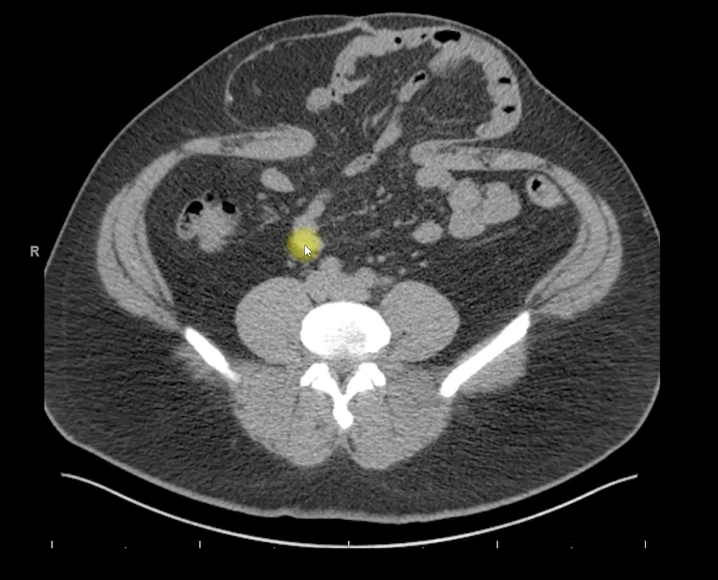

腹部のCTスキャンでは、上腹部の離位4cmとM3ゾーンに8cmのヘルニア欠損が認められました。直筋自体はどちらも約8cmの大きさでした。ヘルニアには閉塞していない小腸のループがあり、嚢への癒着の兆候がありました。

図1。 この患者の腹部骨盤CTの軸方向図で、8cmの筋膜欠損を伴う腹側中央ヘルニアが認められています。ヘルニアの中に小腸の証拠があります。両側の直直筋も見ることができ、こちらも約8cmの大きさです。